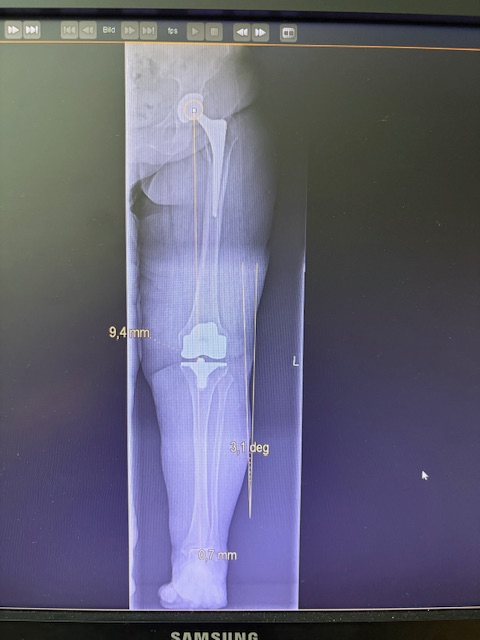

Ο προεγχειρητικός ψηφιακός σχεδιασμός

Πραγματοποιήθηκε σε ειδική ακτινογραφία ολόκληρων των δύο κάτω άκρων. Σε αυτό το ψηφιακό μοντέλο σχεδιάστηκε με ακρίβεια το είδος, το μέγεθος και η ακριβής θέση των προθέσεων, με βάση τα ανατομικά χαρακτηριστικά της ασθενούς.

Ο ψηφιακός σχεδιασμός επιτρέπει απόλυτη εφαρμογή των μοσχευμάτων, ελαχιστοποιώντας τα περιθώρια απόκλισης και εξασφαλίζοντας άριστη ευθυγράμμιση και κινηματική ισορροπία του γόνατος.